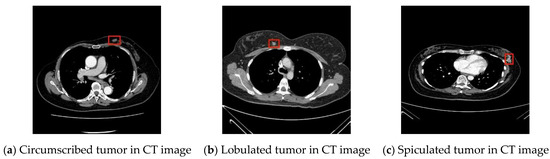

3.6. System Execution Result Evaluation

As for sensitivity for the different tumor types, for circumscribed tumors it was 97.96% (48/49), for lobulated tumors it was 98.89% (89/90), and for spiculated tumors it was 88.57% (31/35). Additionally, the overall sensitivity was 96.55% (168/174). Ten-fold cross-validation was used to evaluate the ability of the classifier to classify benign and malignant tumors. As can be seen from Table 5, accuracy of the trained SVM classifier was 99.43%, AUC value was 0.9941, sensitivity was 98.82%, specificity was 100%, positive predictive value was 100%, and negative predictive value was 98.89%, indicating that the system developed by the study can effectively distinguish benign and malignant tumors. The confidence intervals of AUC and accuracy are calculated at 95% and 99% confidence level, respectively. Regarding the 95% confidence level for the AUC and accuracy, the confidence interval is 0.23 and 0.16, respectively. Regarding © 99% confidence level for the AUC and accuracy, the confidence interval is 0.30 and 0.21, respectively. The system’s result has been shown in the Figure 10.

Figure 10.

Example tumor computer output.